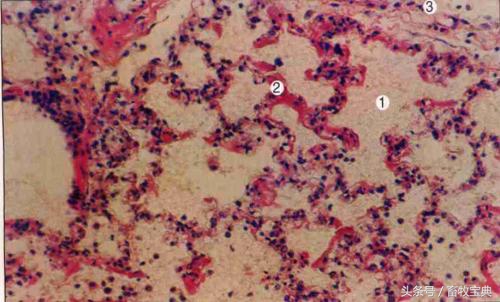

病变 病理特征是各组织器官发生增生性结核结节(结核性肉芽肿)或渗出性炎,或二者混合存在。

剖检在肺脏常见有很多突起的白色结节,切开为干酪样坏死,切开时有砂砾感。有的坏死组织溶解和软化,排出后形成空洞。发生粟粒性结核时,胸膜和腹膜发生密集结核结节,呈粟粒大至豌豆大的半透明灰白色坚硬的结节,形似珍珠状,即所谓的“珍珠病”。